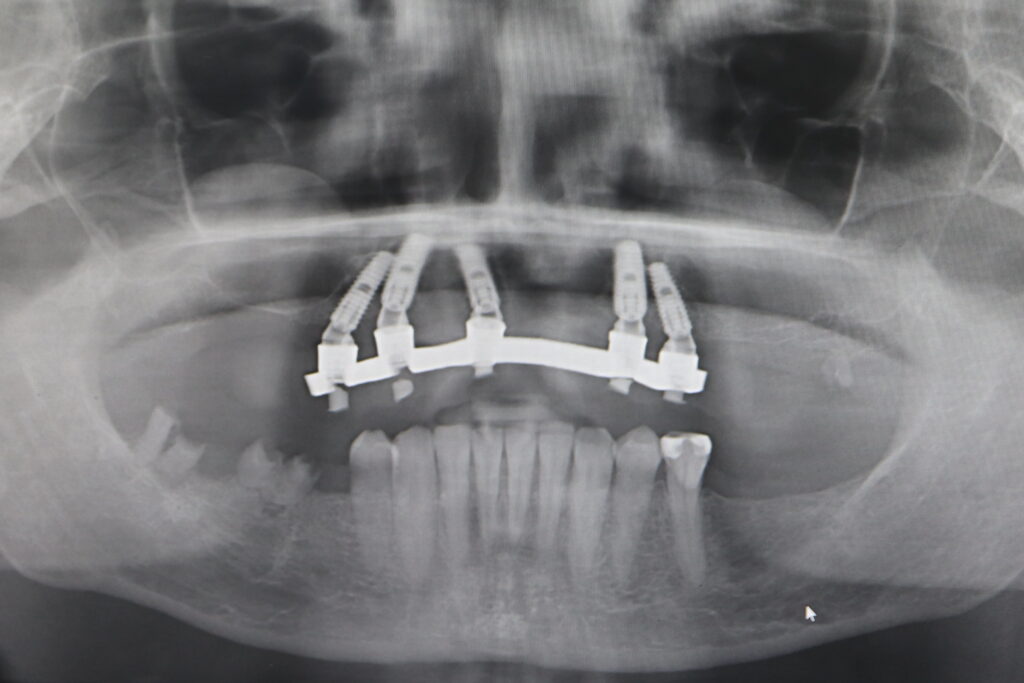

Процесс работы

Что было сделано:

На верхней челюсти были удалены зубы, которые находились в неудовлетворительном состоянии. Удалена киста в области зуба 2.1.

Установлены 5 имплантантов Megagen Anyone и сняты оттиски.

Спустя 5 дней на верхней челюсти зафиксирован протез из пластмассы, армированный металлической балкой из КХС (кобальт-хромовый сплав) с опорой на 5 дентальных имплантатов.